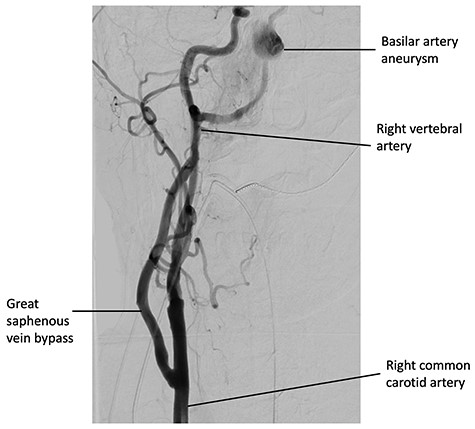

Six weeks after the bypass procedure, the patient underwent an angiogram from the right common femoral artery (Fig. 3). Access to the basilar artery aneurysm was achieved via a coaxial system consisting of a 6F long sheath to the origin of the anastomosis, a 5F intermediate guide within the graft and a 025 microcatheter to deliver a 3 × 35 mm flow diverting Pipeline stent (Medtronic, California, USA) to exclude the basilar artery aneurysm. There were no significant complications and the patient recovered well.

Digital subtraction angiography from the right common carotid artery, demonstrating the CCVAB and decreased filling of the basilar artery after a successful delivery of the pipeline flow diverting stent.